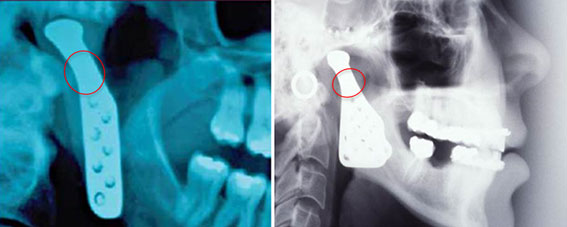

It has been identified that there is a potential risk of the implant fracturing due to a manufacturing fault. If an implant fractured it is highly likely that jaw function will be compromised, and device replacement will be required. The potential fracture sites are circled in the accompanying images of a Narrow TI Mandible Implant (left) and Standard TI Mandible Implant (right).